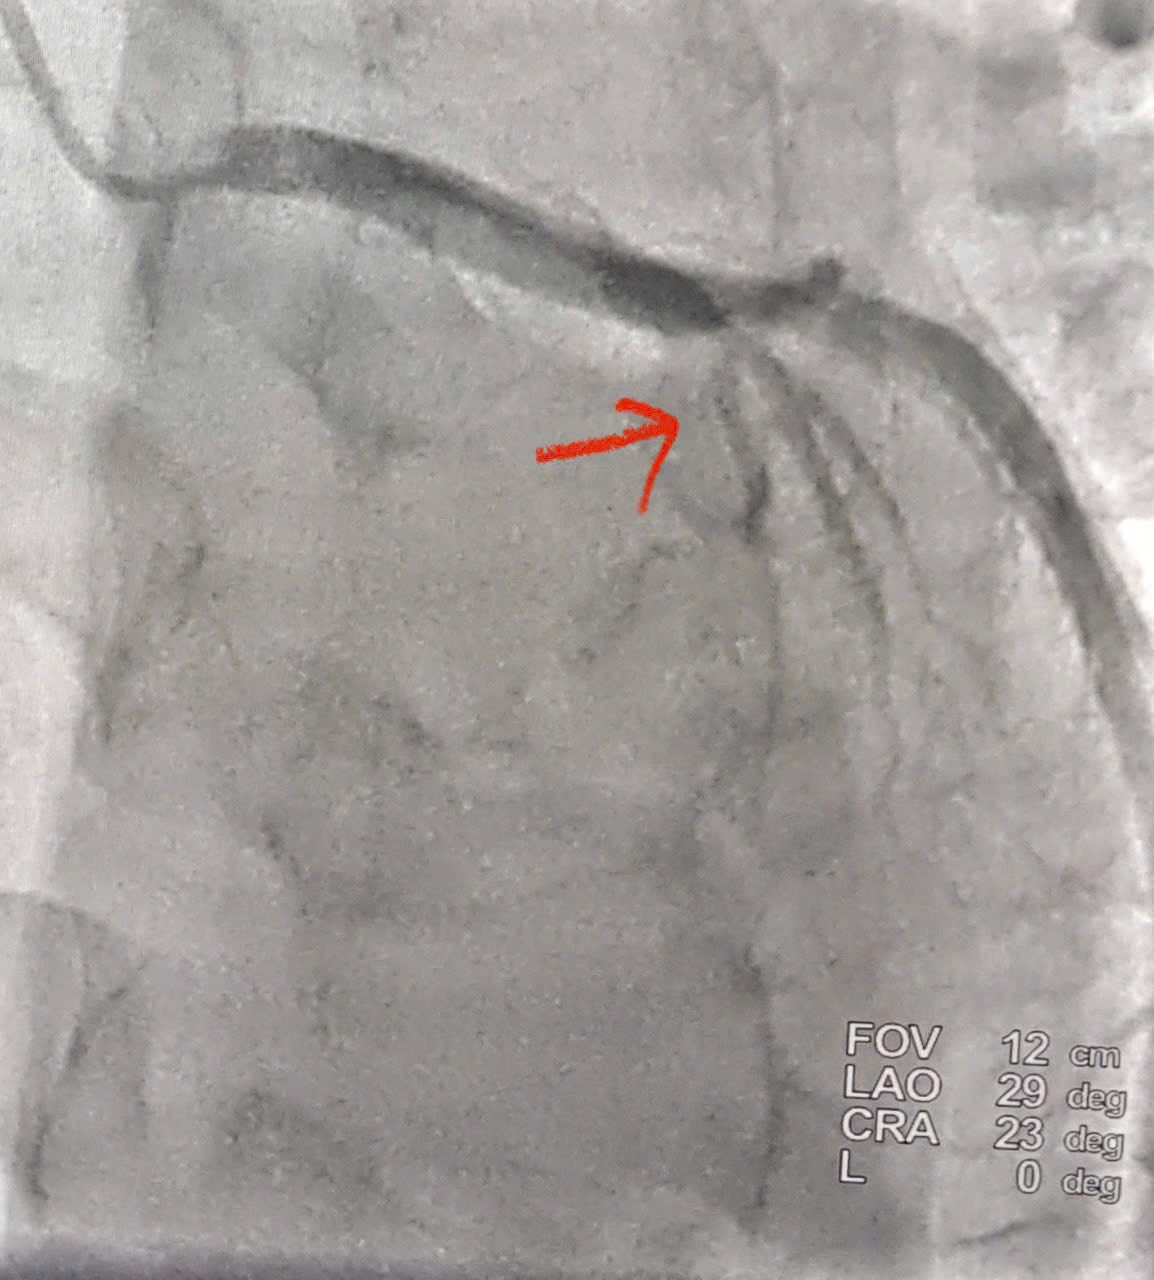

| Hình ảnh tắc động mạch liên thất trước đoạn 2 (LADII) (Hình mũi tên đỏ) |

Bệnh nhân được chỉ định chụp động mạch vành cấp cứu bằng hệ thống chụp mạch số hóa xóa nền (DSA) qua đường động mạch quay phải – phương pháp hiện đại, ít xâm lấn, giúp rút ngắn thời gian can thiệp và giảm biến chứng.

Kết quả chụp mạch cho thấy tắc hoàn toàn động mạch liên thất trước đoạn II (LAD II) – nhánh mạch vành quan trọng cung cấp máu cho phần lớn cơ tim thất trái. Ê-kíp can thiệp đã nhanh chóng tiến hành nong bóng và đặt một stent phủ thuốc tại vị trí tổn thương (Theo hình ảnh minh hoạ). Thủ thuật diễn ra thuận lợi, dòng máu được tái lập ngay sau can thiệp, cải thiện rõ rệt tình trạng thiếu máu cơ tim. Trong cấp cứu nhồi máu cơ tim, yếu tố quyết định là thời gian. Mỗi phút trôi qua là một phần cơ tim bị hoại tử. Việc tái thông mạch vành càng sớm thì khả năng bảo tồn chức năng tim càng cao.